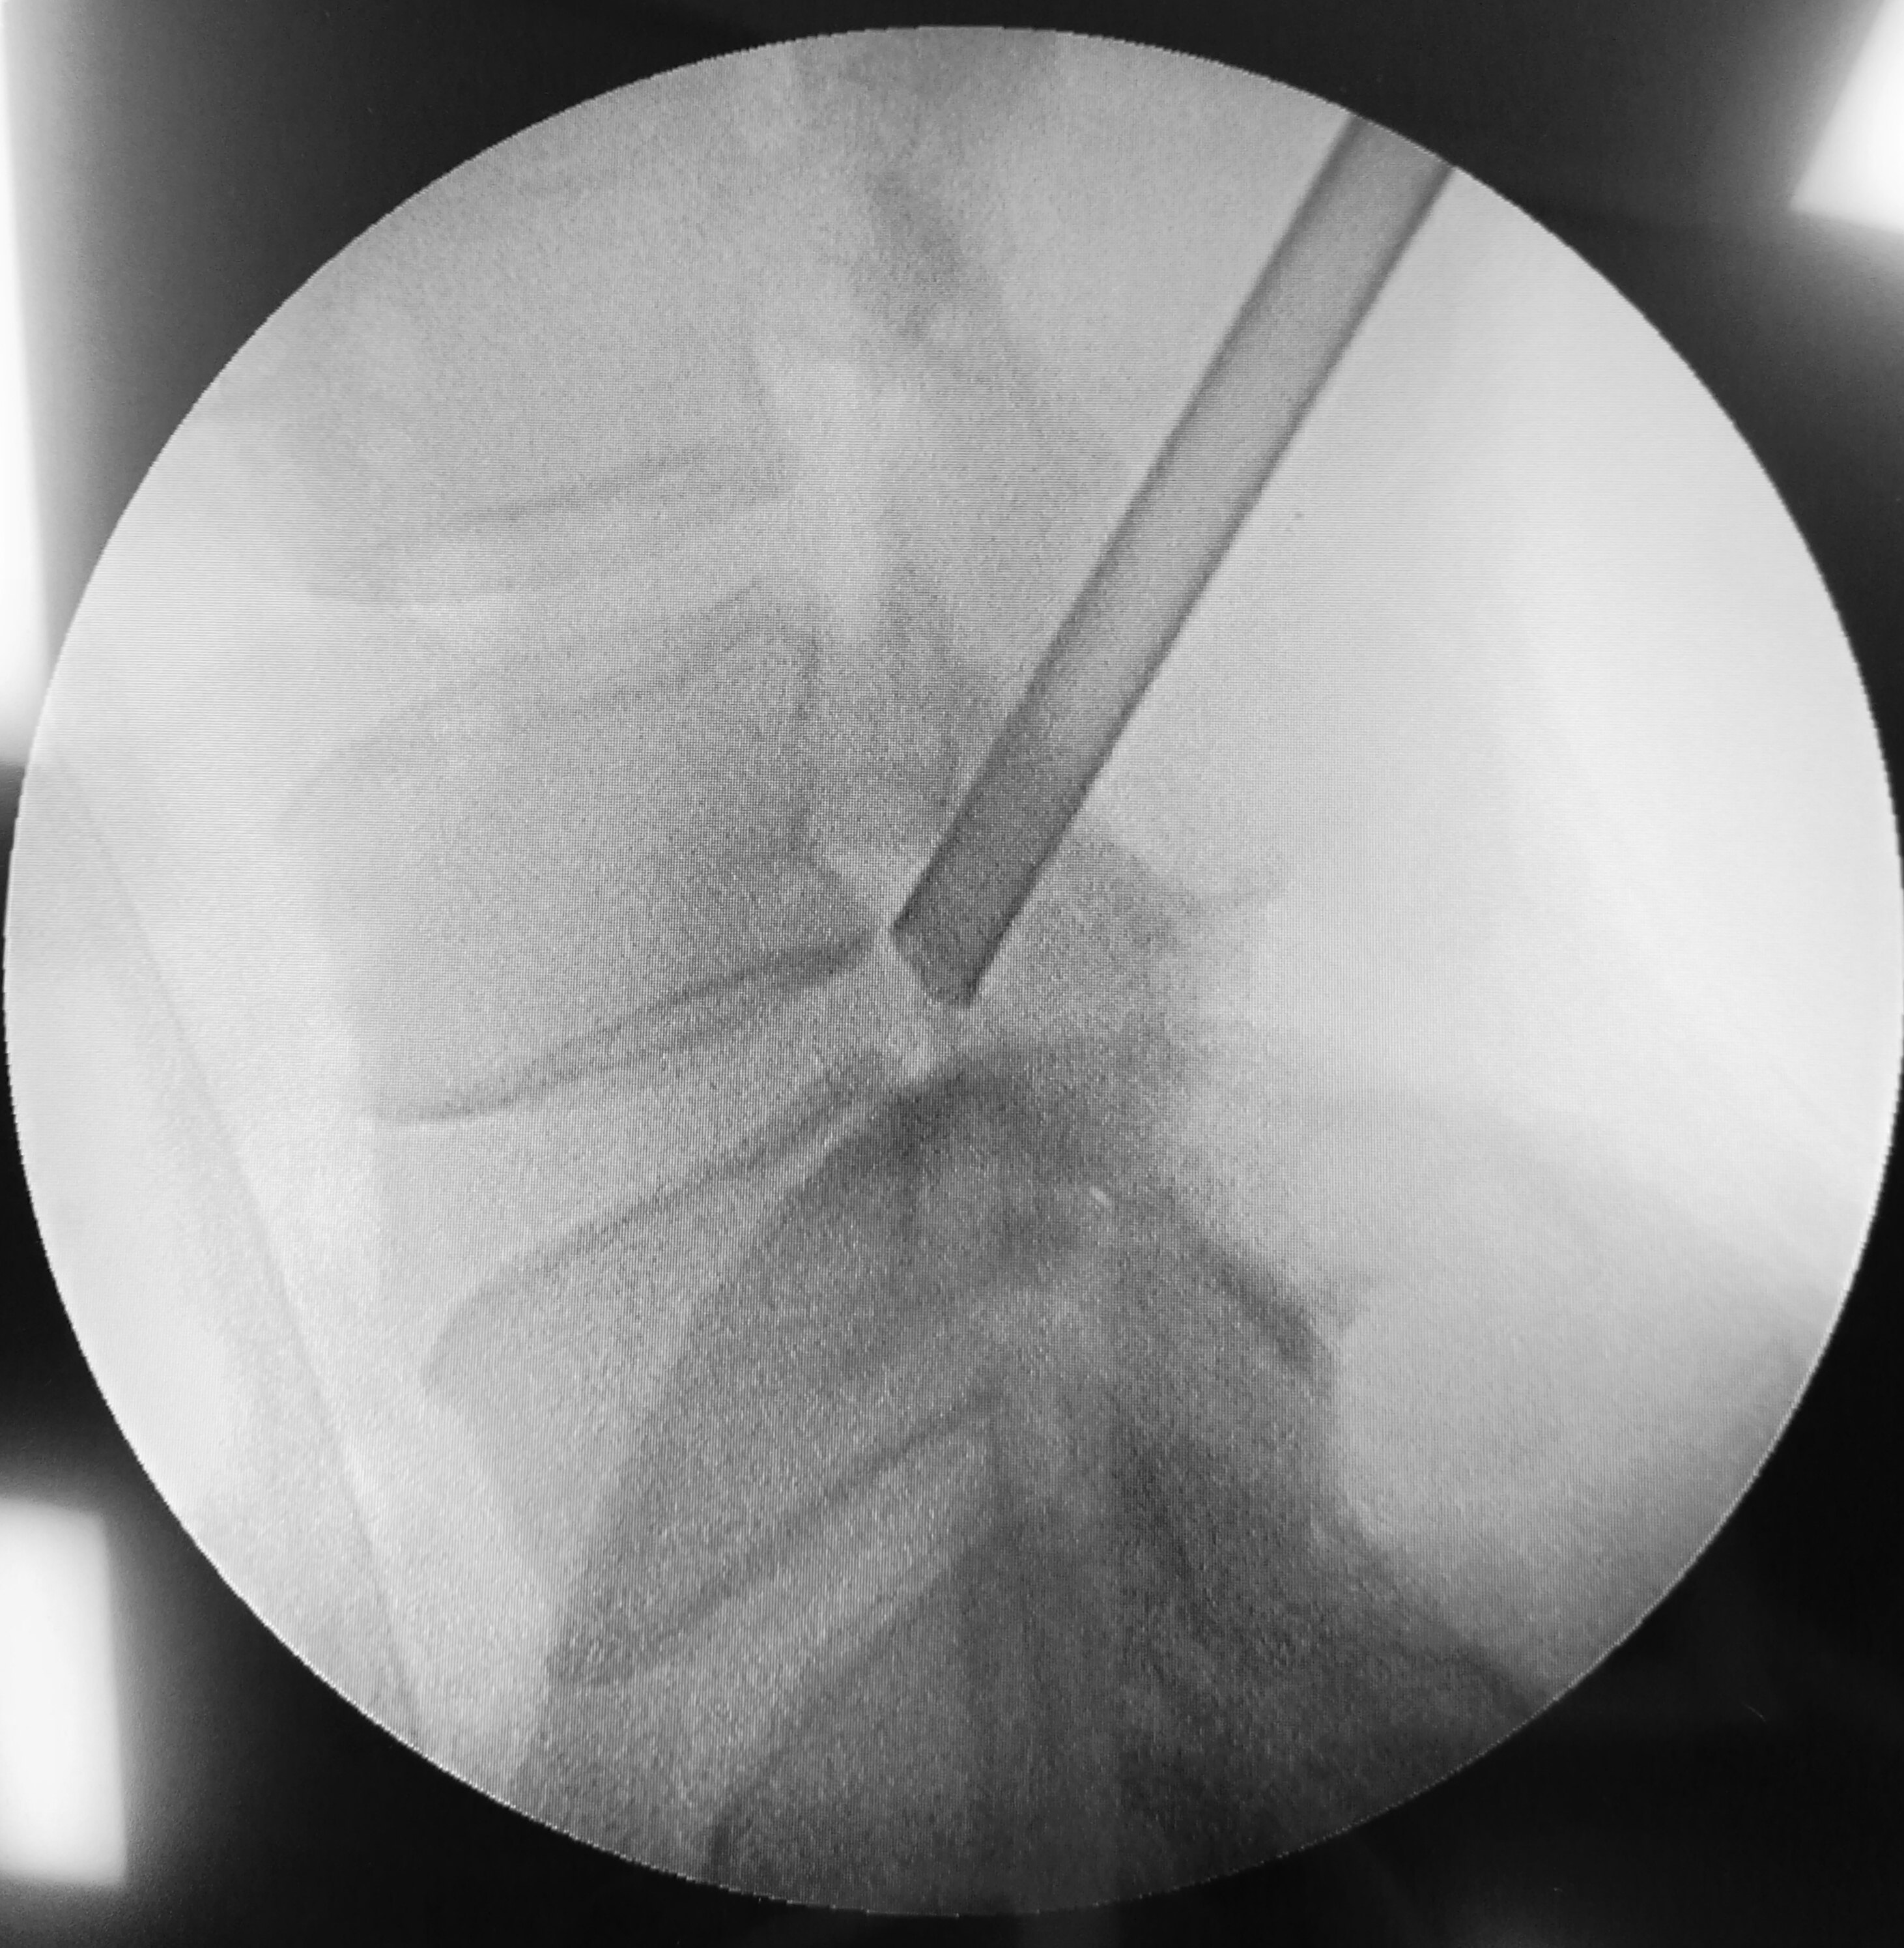

经皮椎间孔镜治疗步骤 - 好大夫在线

图解椎间孔镜手术摘除突出椎间.